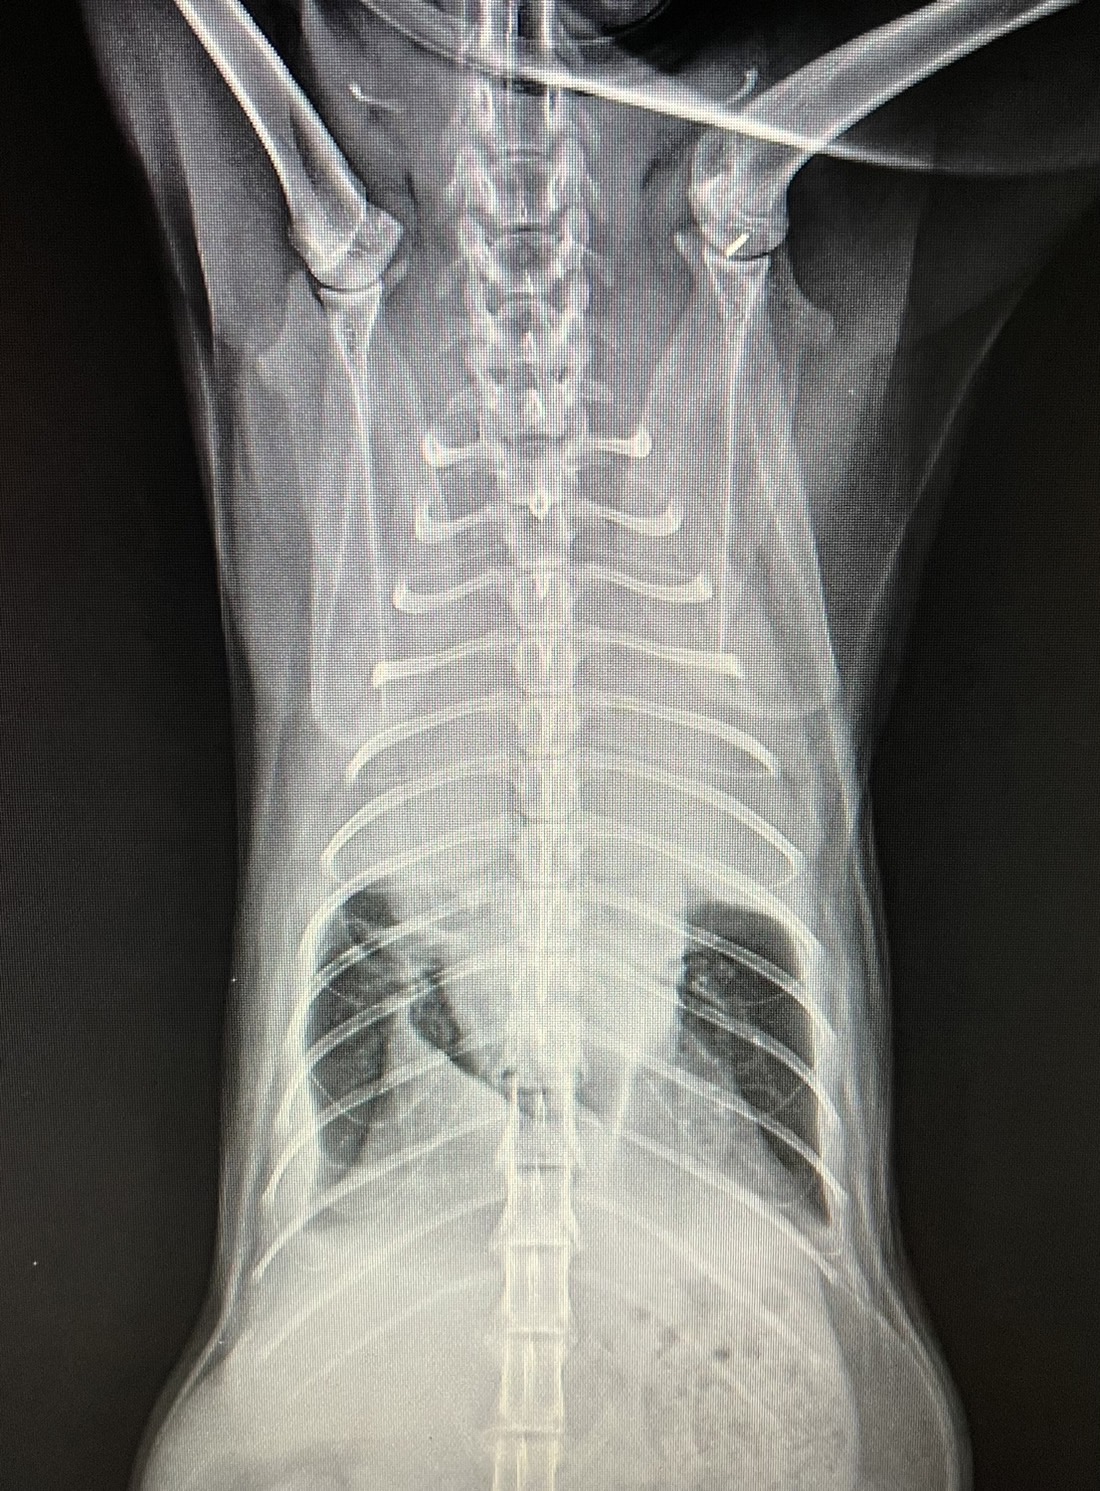

一般我們將胸腔內的積液統稱為胸水,

在以下幾個狀況可能產生:

1.罹患心血管疾病的動物。

2.胸腔內的器官破裂出血時發生胸腔積血,常見於車禍、

墜樓以及胸腔內腫瘤破裂的動物。

3.胸腔內細菌感染造成化膿性液體蓄積,稱為膿胸。

4.腫瘤造成積液,可能為原發性或是身上其他處腫瘤轉移至胸腔。

5.乳糜胸,胸管擴張或破裂導致,通常發生於年輕動物。

胸水的成因有很多種,一旦發現胸水,需要抽出胸腔內液體,

不但可以緩解動物呼吸困難的狀況,

最重要的是可將液體進行分析,視情況需同時進行其他全身檢查,

例如血液學檢查、X光檢查、超音波檢查…,才能找到胸水產生的原因,針對病因進行治療。

若是單純抽出胸水,而沒有找到原因,胸水持續產生會讓動物反覆陷入缺氧的危險當中。